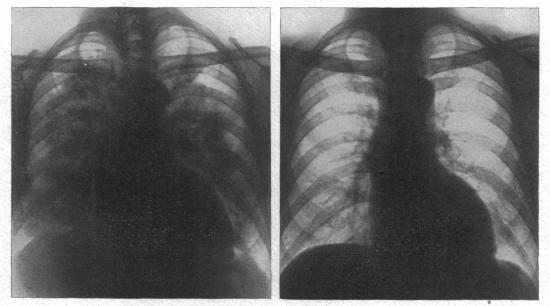

The radiology of acute pulmonary oedema.

Br Heart J. 1951 Oct;13(4):503-18. doi: 10.1136/hrt.13.4.503.